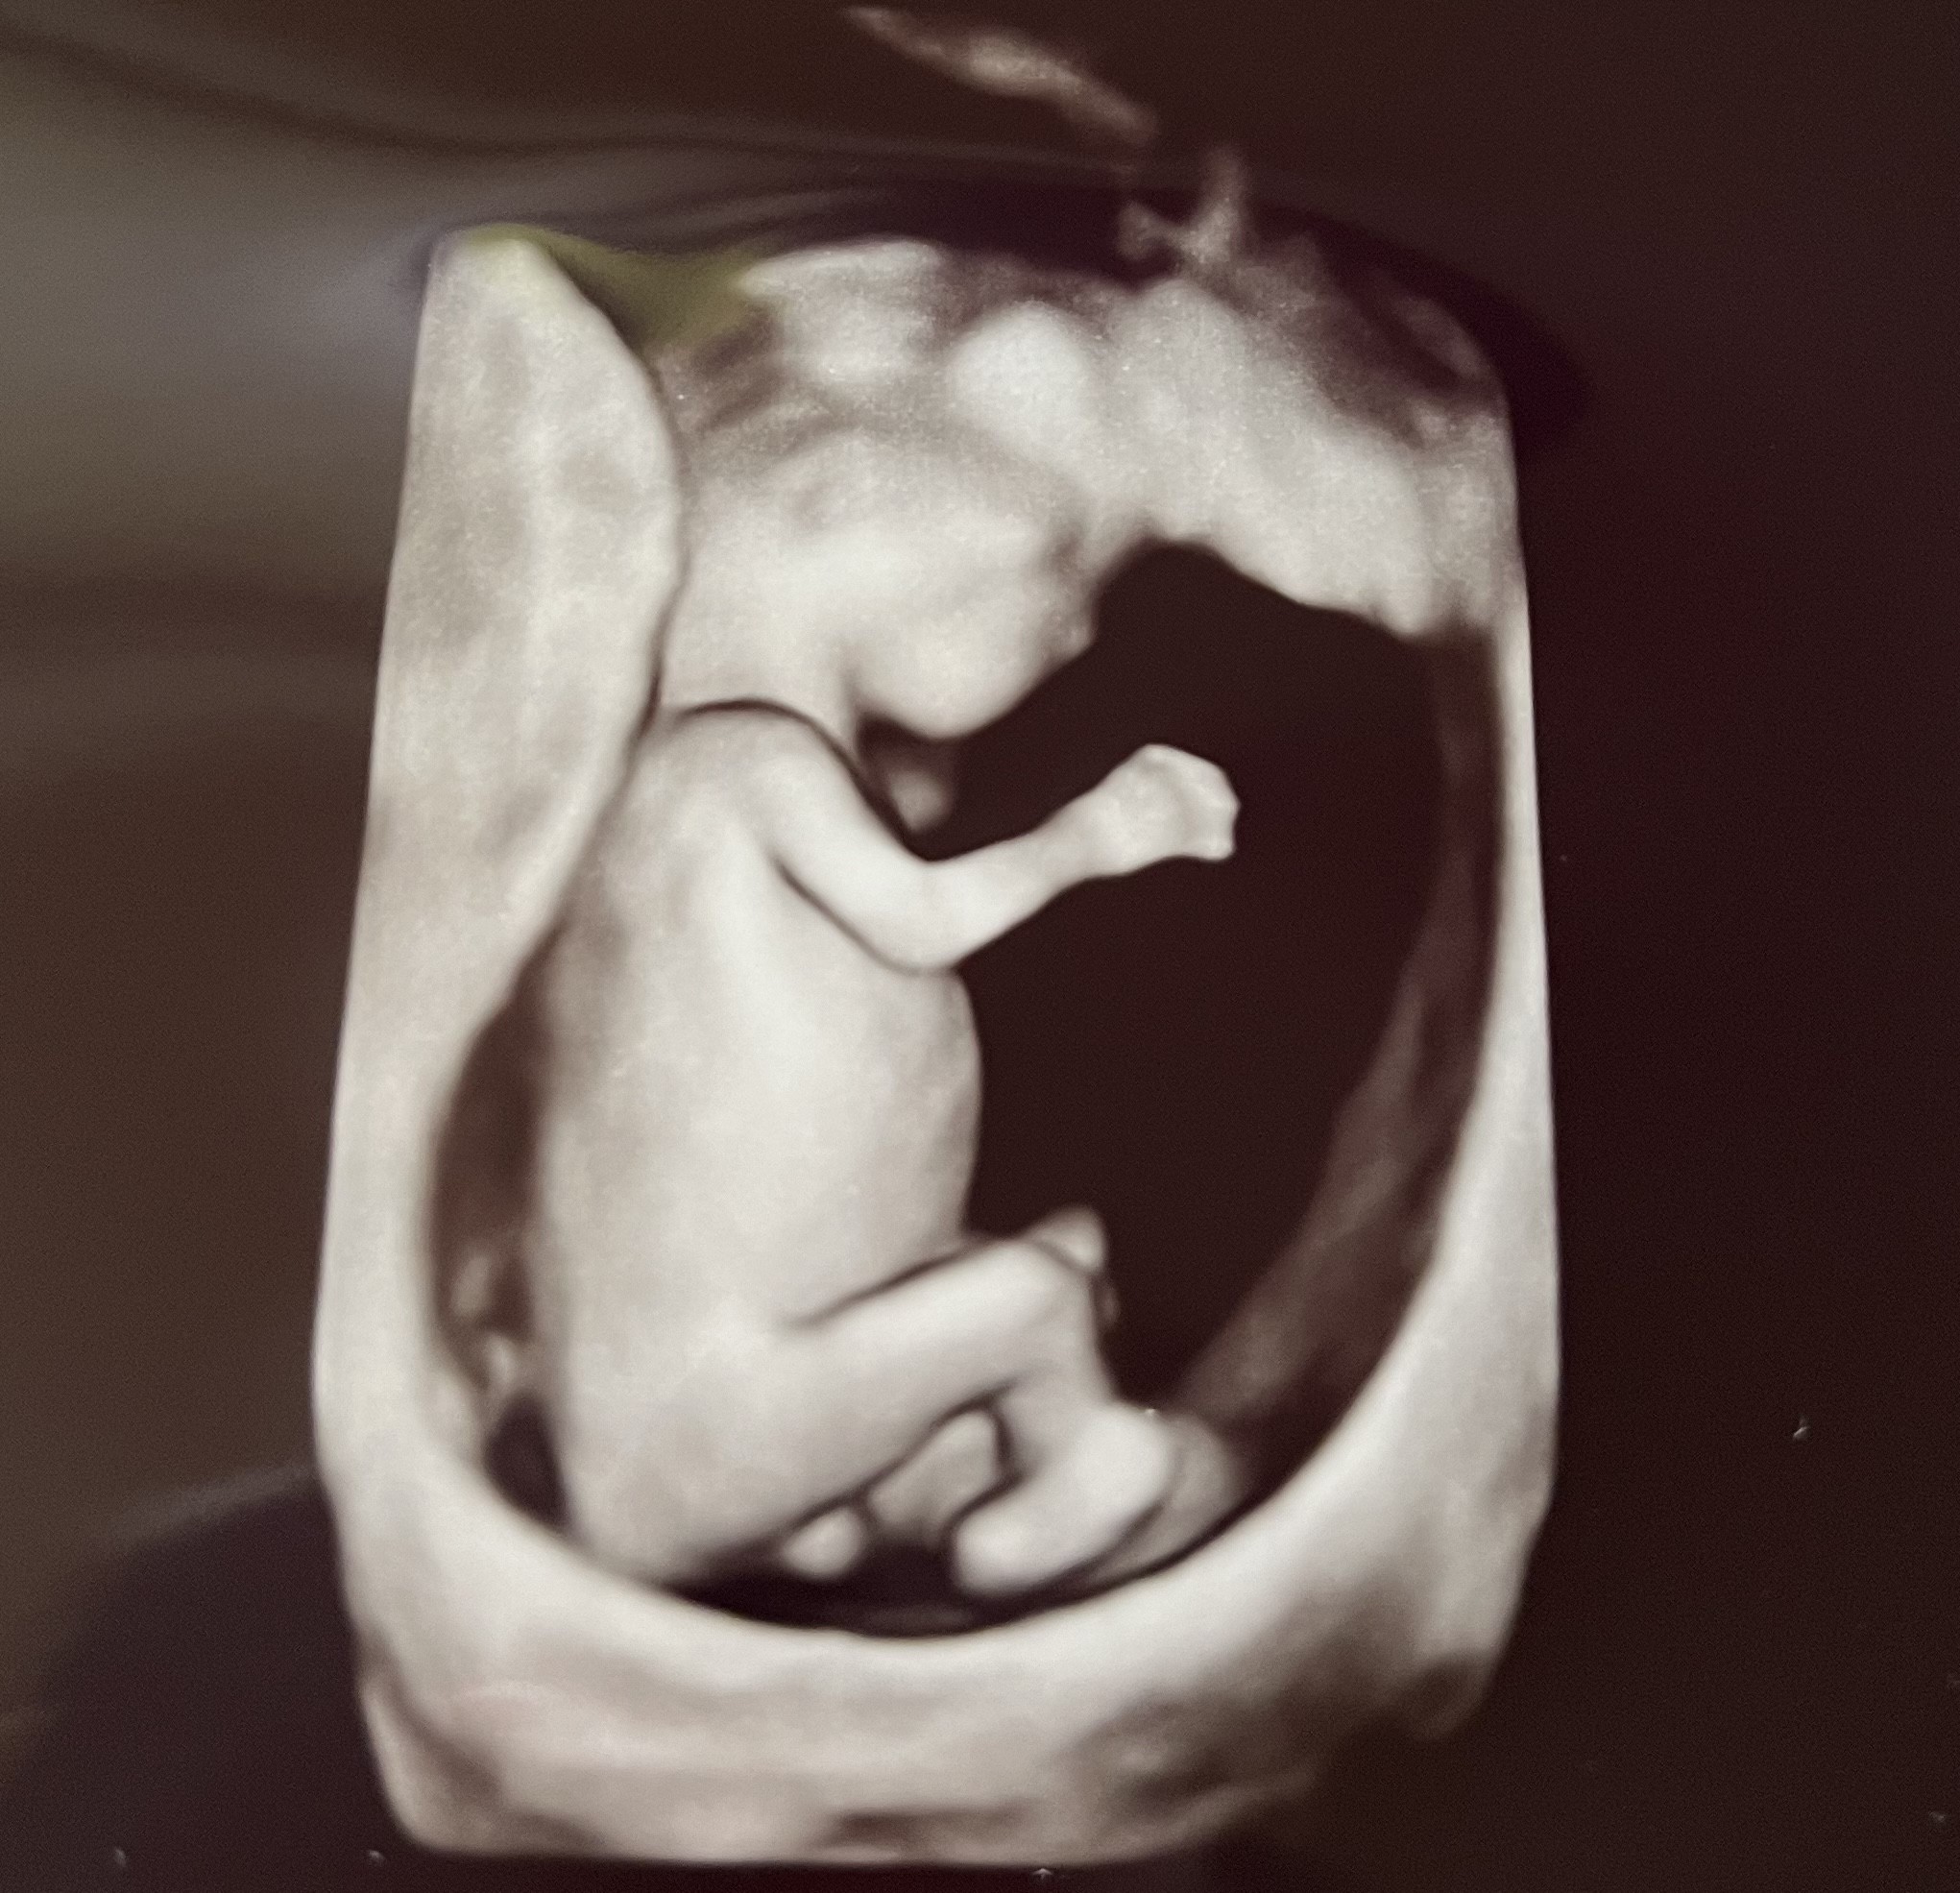

Witam Was 😊 Co ile Wam robią usg? Bo u mnie co 2 wizytę, chodzę prywatnie do ginekologa. Dzieciątko niestety,ale nie chciało się pokazać 😊 Dołączę zdjęcie z usg może Wy coś zobaczycie😊 Pozdrawiam

Też bym obstawiała jądra na tym zdjęciu.

Ja miałam na każdej wizycie co miesiąc, plus dodatkowo pomiędzy wizytami wpadałam do lekarza na szybkie usg bo się schizowałam, że coś nie tak z dzidziusiem... A wszystko z powodu krwawień do 13 tygodnia i kilku lat starań..strach nie opuszczał mnie do końca. A na zdjęciu wygląda jak jąderko 🤭